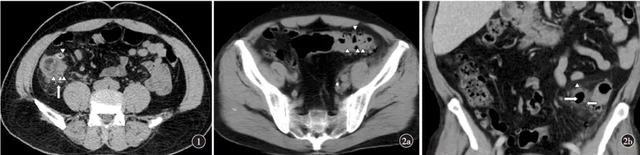

图身体①病例有啥:患者,男性,50岁,CT轴位示回盲部多发憩室(三角箭),邻近肠壁增厚,憩室周围脂肪密度增高、筋膜增厚(长箭),手术病理证实为急性原因阑尾炎合并回盲部多发憩室炎。

图②病例:患者,男性,63岁。②a:CT轴位示乙状结肠多发憩室(三角箭);②b:CT冠状位重组示乙状结肠系膜侧憩室(三角箭),周围脂肪密度增高女人(长箭),憩室周围积气(短箭)。